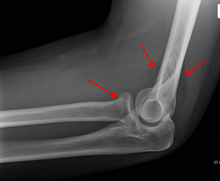

Near the elbow

The upper extremity of the radius (or proximal extremity) presents a head, neck, and tuberosity.

- The radial head has a cylindrical form, and on its upper surface is a shallow cup or fovea for articulation with the capitulum (or capitellum) of the humerus. The circumference of the head is smooth; it is broad medially where it articulates with the radial notch of the ulna, narrow in the rest of its extent, which is embraced by the annular ligament. The deepest point in the fovea is not axi-symmetric with the long axis of the radius, creating a cam effect during pronation and supination.

- The head is supported on a round, smooth, and constricted portion called the neck, on the back of which is a slight ridge for the insertion of part of the supinator muscle.

- Beneath the neck, on the medial side, is an eminence, the radial tuberosity; its surface is divided into a posterior, rough portion, for the insertion of the tendon of the biceps brachii muscle, and an anterior, smooth portion, on which a bursa is interposed between the tendon and the bone.